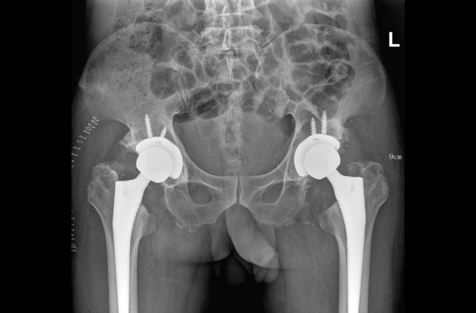

近期pilipili 骨科接诊了一位特殊的患者,58岁,因患有肾病综合征口服激素后出现双侧股骨头坏死20余年,经历了持续的疼痛且活动严重受限,平时无法正常行走。为了解决病痛折磨,慕名找到pilipili 骨科全华山主任。全主任经过详细的查体及影像学检查和评估,确诊为双侧股骨头坏死并双侧僵直髋(髋关节屈伸、内外旋活动均为0°)。骨科专家团队建议患者进行全髋关节置换手术。在手术前,团队成员对患者进行了详尽的解释和专业的心理辅导,详细介绍了手术的具体步骤以及术后的康复流程。为了最大限度地降低手术风险,团队经过一致商议,决定采取分阶段手术策略:首先进行左侧髋关节的置换手术。待左侧术后恢复一个月,再根据患者的具体情况,安排右侧髋关节的置换手术。

手术由全华山主任主刀,手术中切除髋关节周围的骨赘及增生滑膜组织,取出坏死的股骨头,安装了人工全髋关节假体。手术过程顺利,术后第二天,患者就开始在康复治疗师的指导下下床走动。经过一个月的康复训练,患者左髋的疼痛完全消失,能够独立行走,恢复了日常活动。患者对第一次手术效果非常满意,一个月后再次来我院住院行右侧全髋关节置换。

目前患者伤口稳定,已下床行走。经过两次手术,双髋关节疼痛基本消失,活动功能较前明显改善。

术前 术后